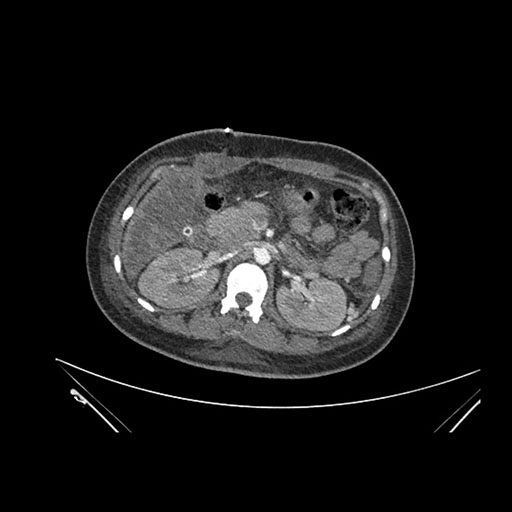

Imaging Analysis

Look through the patient's CT scan to identify any areas of concern for the necessary procedure.

Axial Arterial